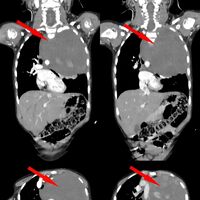

Родители показали дочь врачам, когда заметили у нее небольшую припухлость в области шеи. Специалисты по месту жительства выявили огромное новообразование размером со страусиное яйцо, которое сдавливало сердце и легкое. Сквозь ткань опухоли проходили крупные сосуды: «позвоночная артерия, питающая головной мозг, и подключичная артерия с ее ветвями, питающая левую руку». После телемедицинской консультации ребенка направили в Москву.

Специалист отметил, что благодаря слаженной и кропотливой работе медикам удалось удалить новообразование единым блоком, не нарушив целостность.

«По результатам контрольного гистологического исследования всего объема опухоли были обнаружены злокачественные клетки и установлен точный диагноз — ганглионейробластома», — поделились в пресс-службе.